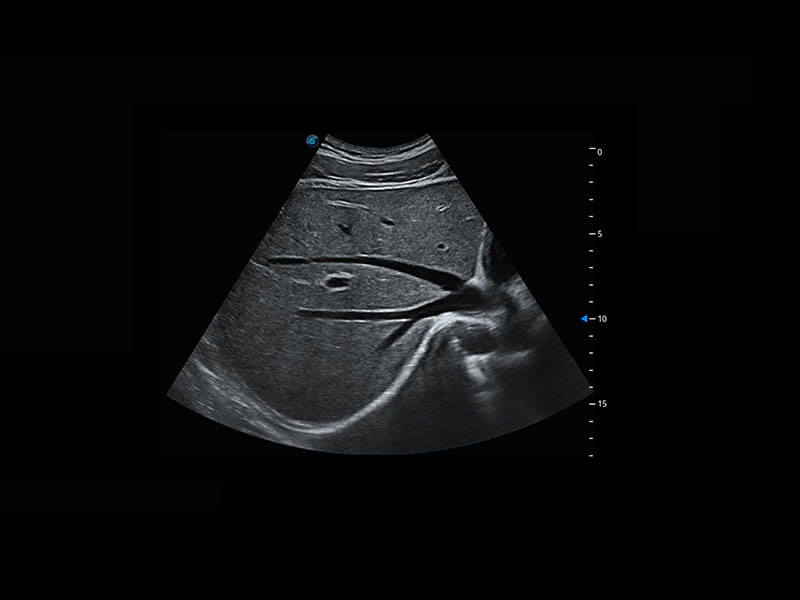

胎儿体循环

光影成像-孕囊